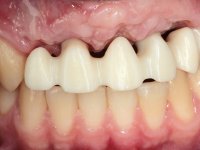

O paciente foi observado conjuntamente e a dúvida que surgiu de imediato foi se seria possível com a regeneração óssea a efectuar poder ser reabilitada naturalmente a zona das papilas interdentárias. Nesse sentido foi feito um enceramento de diagnóstico que contemplaria as duas hipóteses, utilizando ou não a cerâmica gengival. A confecção desse enceramento foi fundamental para expor ao paciente a dificuldade da reabilitação. O wax-up deu origem a um mock-up que foi aprovado pelo paciente e que simultaneamente serviu de guia imagiológica. O caso foi planificado cirurgicamente e realizada uma guia cirúrgica com que foram colocados os implantes. Após 10 semanas foi feita a 1ª impressão para confecção da ponte provisória. Foram criados os primeiros perfis de emergência na gengiva artificial e foi digitalizado o modelo. Por processo de CAD-CAM foi confeccionada uma ponte provisória aparafusada baseada no enceramento de diagnóstico. A ponte trabalhou durante 8 semanas os tecidos moles que foram fielmente copiados numa impressão com técnica de moldeira aberta. Os transferes foram individualizados com resina composta para copiarem fielmente os perfis de emergência criados pela ponte provisória. Confeccionado o modelo de trabalho definitivo, foi realizada uma infra-estrutura em zircónio seguindo a orientação do enceramento de diagnóstico. O assentamento da infra-estrutura foi testado em boca e simultaneamente foi novamente impressionados os tecidos moles com um silicone fluido. Nessa consulta foi feito o levantamento da cor. Os dentes 13 e 23 apresentavam uma saturação anormalmente forte que resolvemos não valorizar, optando por privilegiar a relação com o sector antero-inferior. Foi realizada uma nova gengiva artificial com a impressão que acompanhou a impressão de arrasto com a infra-estrutura. Após a colocação da cerâmica na infra-estrutura foram coladas as meso-estruturas. O trabalho final foi aparafusado lentamente permitindo a adaptação dos tecidos moles.